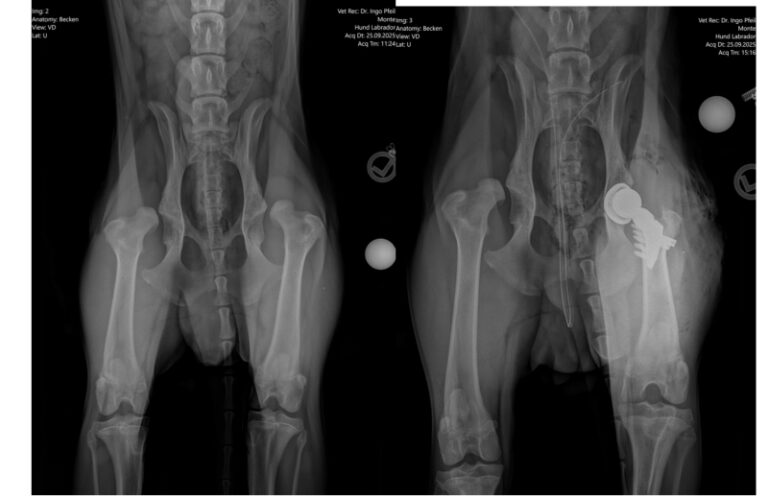

Leider stellte Dr. Pfeil in der Tierklinik fest, dass sich die Hüften innerhalb der letzten vier Wochen derart verschlechtert hatten, dass eine DARthroplastik nicht angewandt werden konnte und nunmehr beide Hüften durch künstliche Gelenke ersetzt werden müssen. Als erste OP wurde nun das linke Hüftgelenk ersetzt. Alles ist gut gelaufen und das Entscheidende ist nun der Heilungsprozess, was bei so einem Wirbelwind eine große Herausforderung darstellt.

Nachdem Monte immer mehr Auffälligkeiten beim Laufen zeigte, wurde er durch seinen Besitzer in einer Tierarztpraxis vorgestellt. Die Diagnose war sehr ernüchtern: Beidseitige schwere HD. Nur eine Operation kann dem jungen Tier helfen. Dazu war der Herr allerdings nicht bereit und holte ihn einfach nicht mehr aus der Tierarztpraxis ab. Er war der Meinung, dass Monte eingeschläfert werden sollte. Natürlich war das keine Option für die Tierärztin und so machte sie sich auf die Suche nach Hilfe. Vermittlungsversuche blieben erfolglos und die Unterbringung in einer Tierpension konnte nicht ewig aufrechterhalten werden. Dann der Anruf bei uns.

Monte ist dem Alter entsprechend einen Frohnatur. Er genießt das Leben im großen Hunderudel und mit seinen neuen Menschen. Aufgrund seiner Schmerzen benötigt er oft Ruhepause und sehr lange Spaziergänge sind nichts für ihn. Da wir dem Jungspund so schnell wie möglich helfen wollen gesund durch die Gegend flitzen zu können, haben wir uns mit dem Operateur von Sera, Dr. Pfeil in Dresden, in Verbindung gesetzt. Da Monte noch sehr jung ist, wäre eine spezielle OP, eine sogenannte DARthroplastik, möglich. Diese Operation könnte an beiden Hüften gleichzeitig durchgeführt werden und die Heilungsaussichten sind sehr gut.